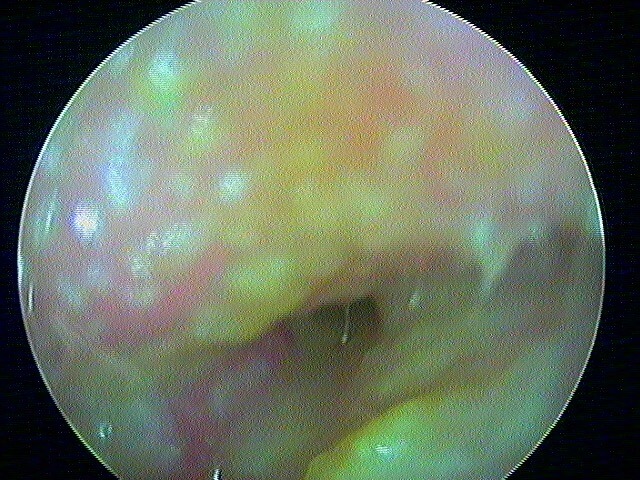

10/1 Cholestéatome acquis (secondaire)

Epithélium stratifié, kératinisé et squameux présent dans l’oreille moyenne, "croissance progressive de peau dans l’oreille", "skin in the wrong place": la peau malade du tympan va détruire tout sur son passage: le tympan lui-même, les osselets, le cadre osseux jusqu'à la méninge. Là il faut bien utiliser toutes ses connaissances sémiologiques d'otoscopie pour faire le diagnostic, qui est plus facile que l'otite atéléctasique, en raison de la présence de squames.

Cela touche adultes & enfants.

Le/la patient·e avait attendu quelques mois avant de revenir: le cholestéatome a englobé tout le malléus: